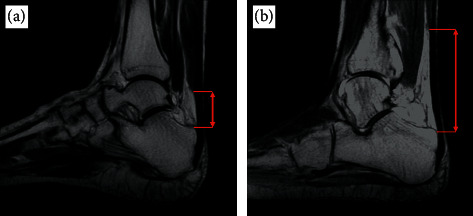

Objectives: The free Achilles tendon is defined as the region of tendon distal to the soleus which is "unbuttressed," i.e., unsupported by muscular tissue. We reasoned that a relative lack of distal buttressing could place the tendon at a greater risk for developing Achilles tendinopathy. Therefore, our primary goal was to compare the free Achilles tendon length between those with midportion or insertional Achilles tendinopathy and healthy controls.

Design: This is a retrospective case-control study. Setting. Hospital in Vancouver, Canada. Participants. 66 cases with Achilles tendinopathy (25 insertional, 41 midportion) consecutively drawn from a hospital database within a 5-year period and matched to 66 controls (without tendinopathy) based on sex, age, and weight. Main outcome measures. Odds ratio of the risk of developing Achilles tendinopathy given the length of free tendon, defined anatomically on MRI, after adjustment for confounders.

Results: MRI-defined free Achilles tendon length is a statistically significant predictor of having midportion Achilles tendinopathy (odds ratio = 0.53, 95% confidence interval 1.13 to 2.07). Midportion Achilles tendinopathy cases had significantly longer free tendons (Mdn = 51.2 mm, IQR = 26.9 mm) compared to controls (Mdn = 40.8 mm, IQR = 20.0 mm), p = 0.007. However, there was no significant difference between the free Achilles tendon lengths in insertional AT cases (Mdn = 47.9 mm, IQR = 15.1 mm) and controls (Mdn = 39.2 mm, IQR = 17.9 mm), p = 0.158. Free Achilles tendon length was also correlated with the tendon thickness among those with Achilles tendinopathy, rτ = 0.25, and p = 0.003.

Conclusions: The MRI-defined length of the free Achilles tendon is positively associated with the risk of midportion Achilles tendinopathy. A relative lack of distal muscular buttressing of the Achilles tendon may therefore influence the development of tendinopathy.